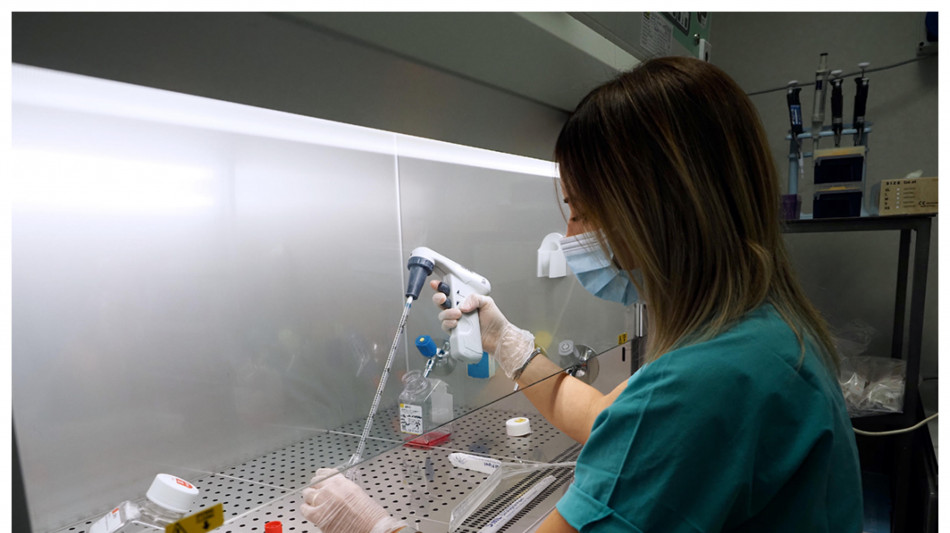

Bioplast, ricostruire ossa e cartilagini dalle cellule staminali

Ricerche nel laboratorio di ricerca del Policlinico di Palermo